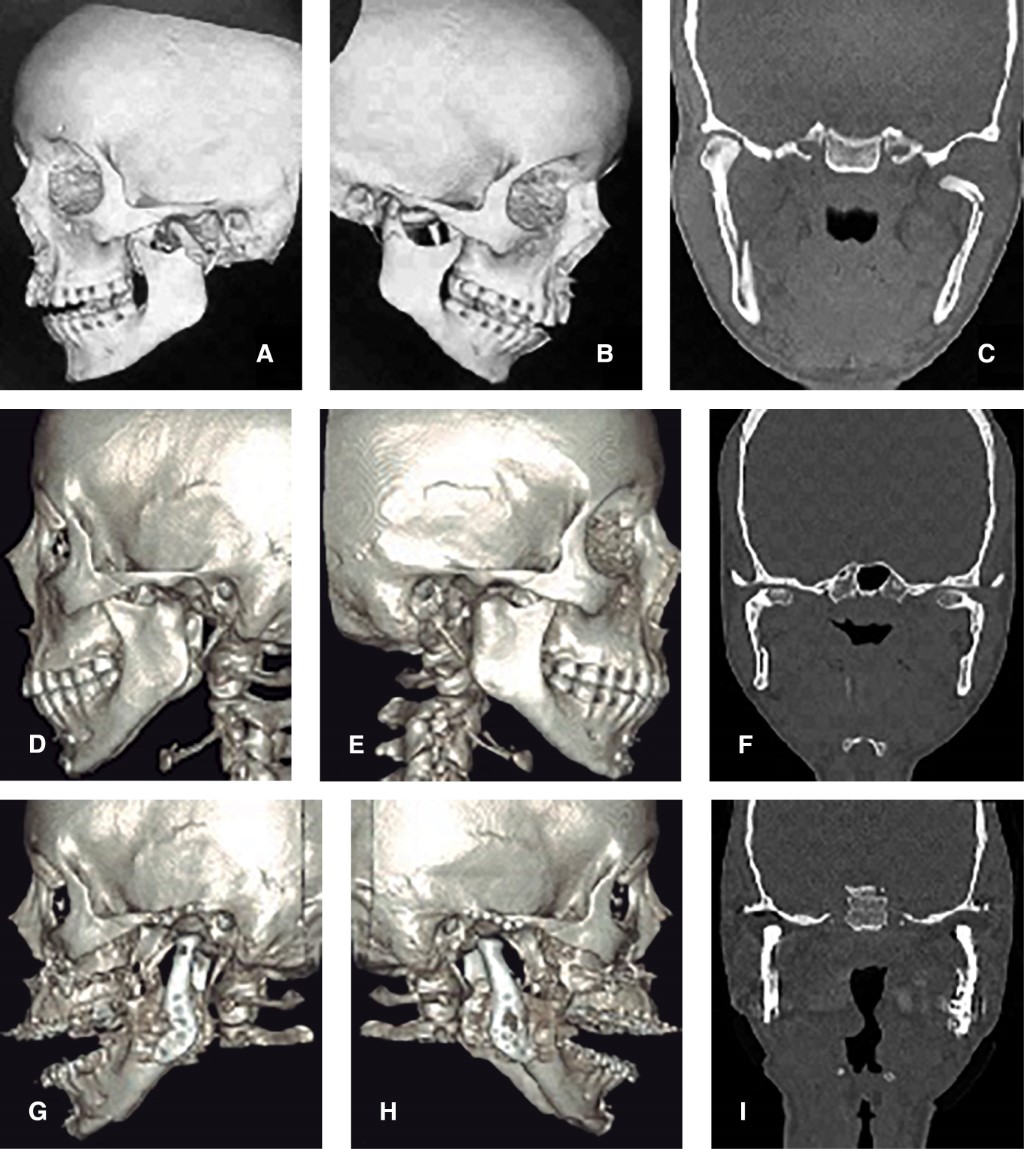

Paciente femenino de 22 años con diagnóstico de fractura subcondilar bilateral y sínfisis mandibular secundaria a caída en bicicleta, tratada mediante RAFI de sínfisis concomitante con manejo cerrado con arcos de Erich y guía elástica clase II para mantener oclusión.

En el cuarto mes postoperatorio, fue remitida por pérdida progresiva de altura facial posterior, perfil facial convexo y apertognatia. La tomografía mostraba una posición medial del cóndilo bilateralmente con respecto a la fosa glenoidea (Figuras 5 y 6). Se propuso reemplazo de ATM bilateral con prótesis customizada concomitante con CO, consistente en avance maxilar de 4 mm con descenso posterior de 5 mm, avance mandibular de 10 mm y mentoplastia de avance 4 mm de avance.

Con tres años de seguimiento, el tratamiento devolvió función masticatoria y proyección del tercio inferior, sin dolor articular.

Figura 5

Figura 6